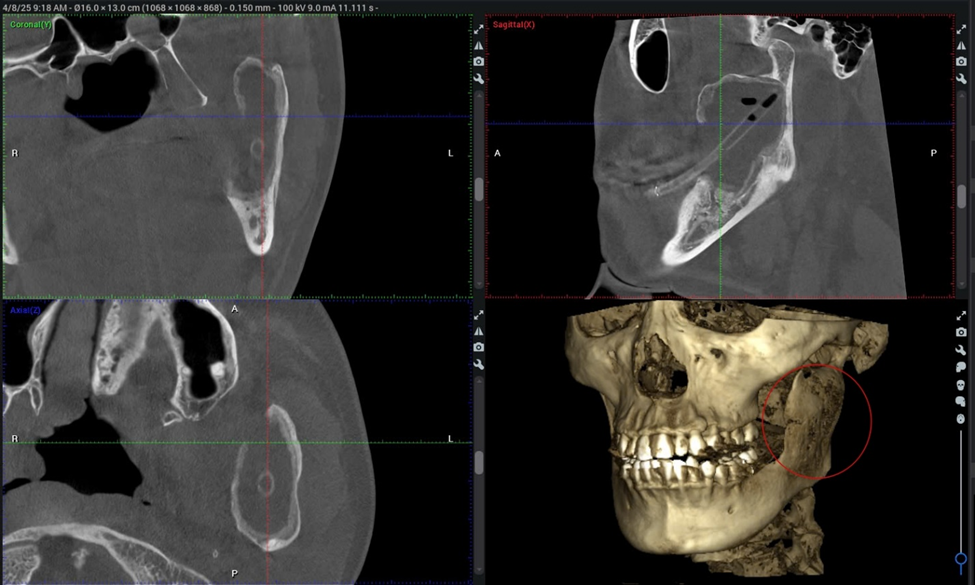

តាមរយៈការស្កែន CBCT (Cone Beam Computed Tomography) លោកវេជ្ជបណ្ឌិត ង្វៀថាញ់ទុង ប្រធានផ្នែកទន្តសាស្ត្រ និងវះកាត់ ថ្គាមមុខ នៃមន្ទីរពេទ្យ FV បានរកឃើញរបួសដែលបំផ្លាញឆ្អឹងថ្គាមក្រោមស្ទើរតែទាំងស្រុងពីតំបន់មុំថ្គាមរហូតដល់ Condyle ។ លោកវេជ្ជបណ្ឌិត ទុង បានមានប្រសាសន៍ថា«ថ្គាមទាល់លេខ៣៨របស់អ្នកជំងឺដុះជាប់នឹងដុំសាច់ នេះអាចជាមូលហេតុមួយដែលនាំឱ្យកើតដុំសាច់»។

ជាសំណាងល្អ ដុំសាច់នេះនៅតែក្នុងទីតាំងនៃតំបន់ឆ្អឹង អ្នកជំងឺមិនស្ពឹកចង្កា និងបបូរមាត់ខាងក្រោម (បង្ហាញថាសរសៃប្រសាទធ្មេញក្រោមមិនខូចខាត) ហើយអ្នកជំងឺនៅតែអាចបើកមាត់បានជាធម្មតា ទោះបីជាដុំសាច់បានរាលដាលដល់តំបន់សន្លាក់ថ្គាម temporomandibular ក៏ដោយ។ សញ្ញាទាំងនេះបង្ហាញថាការព្យាបាលបែបថែរក្សាទម្រង់ដើមអាចធ្វើទៅបានសម្រាប់អ្នកជំងឺ។

បន្ទាប់ពីការព្យាបាលរយៈពេល ៣ ខែ ដុំសាច់បានរួមតូចបន្តិច ស្រទាប់ឆ្អឹងថ្មីដែលមានកម្រាស់ប្រហែល ២-៣mm បានបង្កើតឡើងយ៉ាងច្បាស់នៅជុំវិញប្រហោងនៃដុំសាច់។ ក្នុងអំឡុងពេលនៃការតាមដាននៅខែមេសា ឆ្នាំ២០២៥ អ្នកជំងឺបានរីករាយប្រាប់ថាគាត់អាចញ៉ាំ បើកមាត់បានធម្មតា និងស្ទើរតែគ្មានការឈឺចាប់។